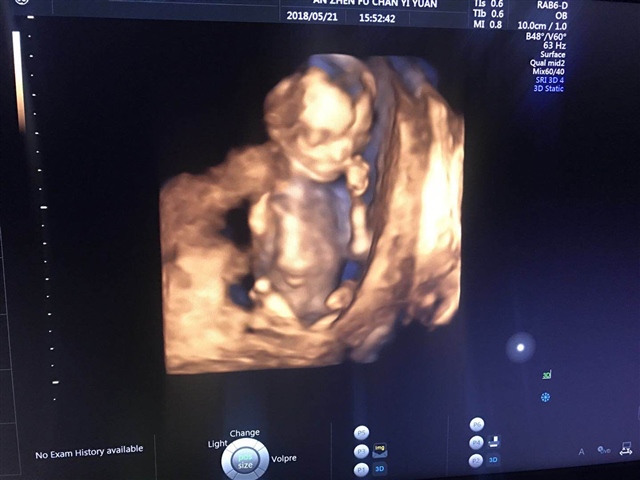

看着像男孩,

雪梨

孕10周+1天